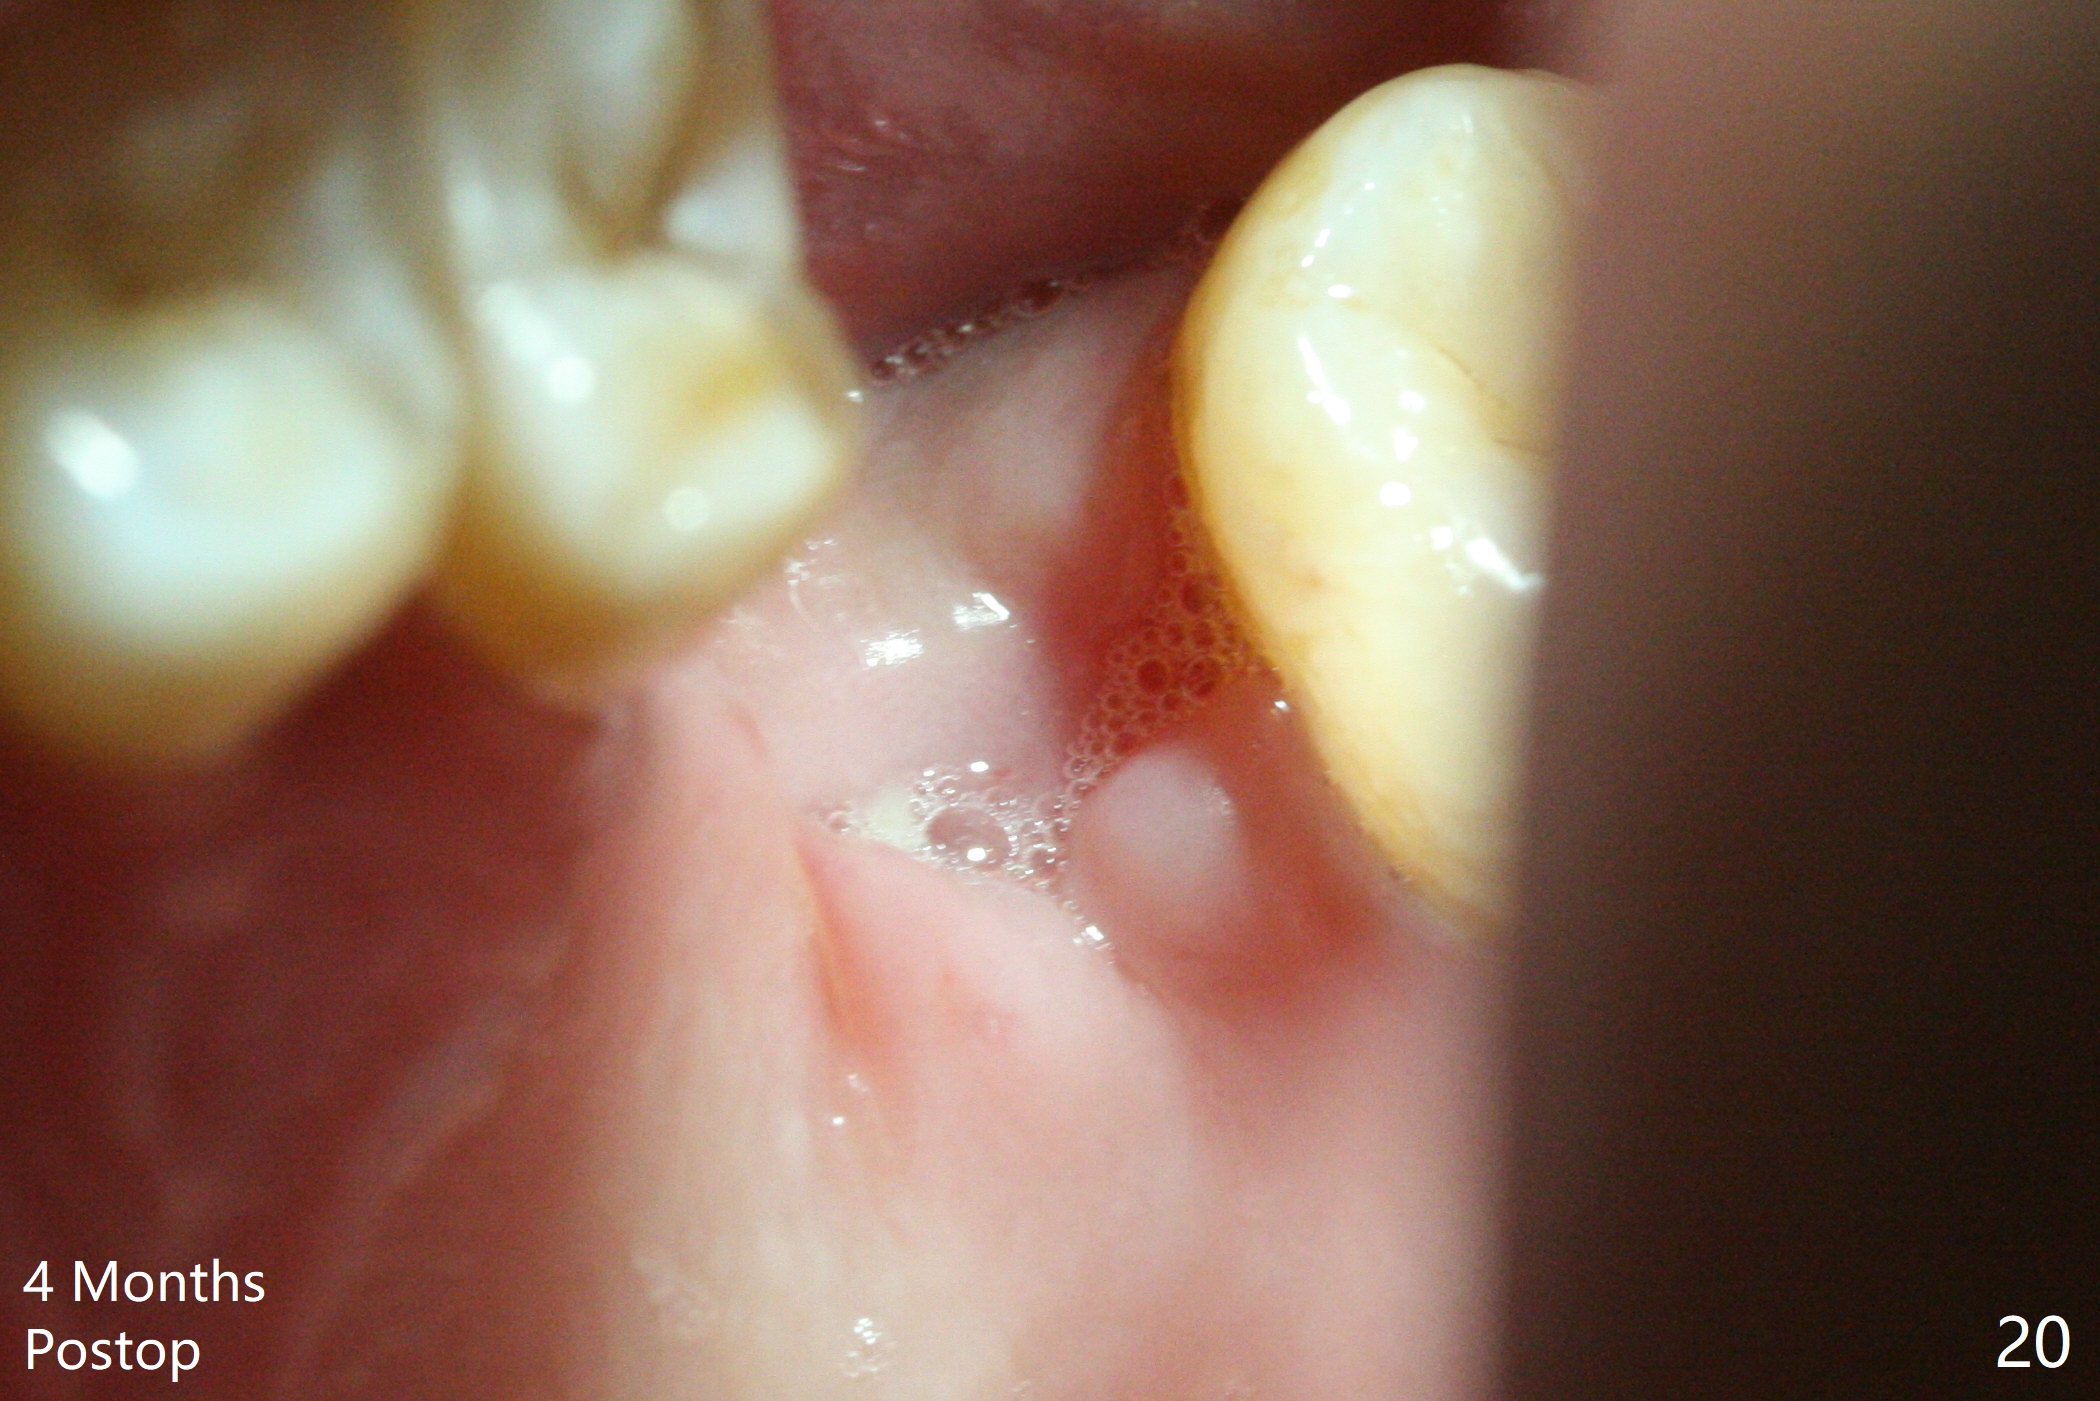

Poor visibility for immediate implant in the molar region is another contributing factor for the dislodgement.  The patient returns for follow up 15 days (Fig.15) and 1 month (Fig.16) postop.  Bone graft seems to be stable around the implant.  The socket heals 4 months postop (Fig.20).  The implant seems to have been osteointegrated (Fig.17,18).  It will be backed up for ~ 3 mm to improve implant/crown ratio (Fig.19, as compared to Fig.14).  If it cannot be done, take impression immediately and make a subgingival provisional before suturing.